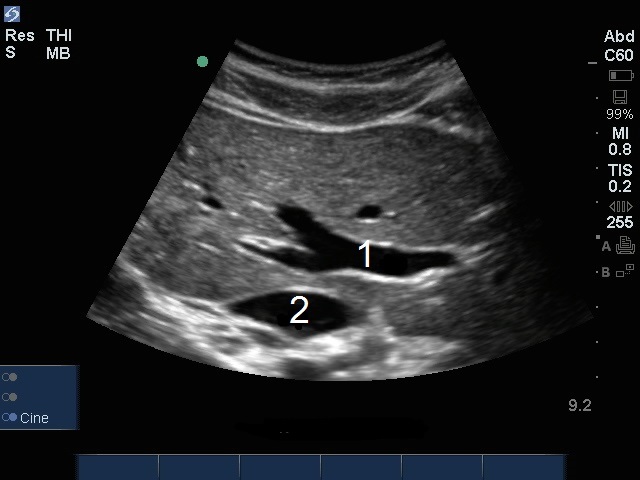

肝門脈画像

門脈(PV)

下大静脈(IVC)